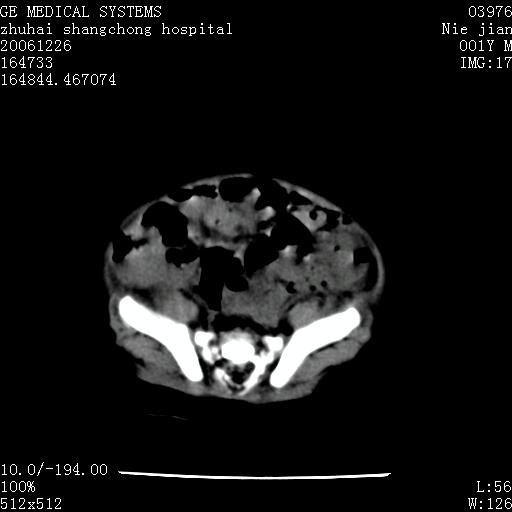

3个月婴儿腹胀来看。

肝各叶比率失调,明显增大,实质内大量脂肪侵润。另:左侧肾上腺区较大类圆形低密度肿块,左肾明显受压 下移。多考虑:1 左侧肾上腺神经母细胞瘤!2 肝弥漫性损伤!

肝各叶比率失调,明显增大,实质内见多发团块状低密度灶。另:左侧肾上腺区较大类圆形肿块,左肾明显受压 下移。多考虑:1 左侧肾上腺神经母细胞瘤!2 肝脏多发转移!

鉴别诊断:肾母细胞瘤,好发1-3岁,肾母细胞瘤是发生在肾脏,又称肾胚瘤,肾脏本身增大。而神经母细胞瘤也称成神经细胞瘤,好发1-2岁,多发生在肾上腺髓质。肾脏本身表现受压向下移位。

【影像特征】

1、肝明显增大,肝弥漫性低密度灶。

2、肾上腺区见类圆形肿块,其内密度不均,见片状偏高密度。

【诊断】

1、肝弥漫性病变,考虑急性肝炎致广泛脂肪浸润可能性大。

2、肾上腺区占位,假性肿瘤?肾上腺血肿(感染所致)?

1、关键着眼点:肝脏弥漫性病变内有没有走形的血管,仔细看部分低密度内有血管影(要有增强扫描作为证据就好了),说明并非肿瘤样病变,而是脂肪浸润。即可能不是转移瘤或原发肿瘤,低密度的形态上看,是片状,也不像肿瘤。

2、儿童肝炎最常见的是感染,有时食入性损害或药物也可致肝脏炎症,肝炎致大空泡型脂肪变性,是一种无痛性疾病,无症状,病因有营养异常、代谢性疾病、药物及病毒感染。所以脂肪变性与感染有关。

3、肝炎的结局是肝硬化,而恰恰一年后复查,已有肝硬化表现。肿瘤一般那会消失,那叫奇迹。

4、肾上腺出血也可见于败血症及感染,通常包块在数周内消失,ct表现包块内有偏高密度,可能是亚急性血肿的表现。假性肿瘤即腹部肠管积液、扩张血管及邻近结构的伪像。自然会消失。

5、因此,感染可以贯穿一切,解释一切。肿瘤自然消退?可能吗?那些应要无道理的创造奇迹的事情会那么容易发生吗?